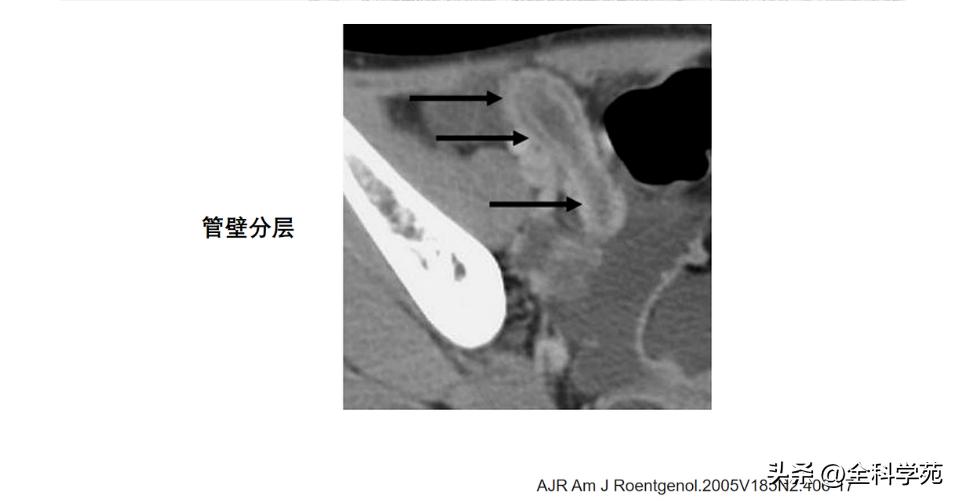

◆ 阑尾壁增厚

>3mm

CT: 阑尾壁明显增强

MRI: T1低信号,T2高信号,DWI: 扩散受限

6-10 mm 伴阑尾壁增厚、壁明显强化,周围脂肪间隙模糊或分层(靶征或牛眼征,表明粘膜下水肿的液体含量vs 气体含量